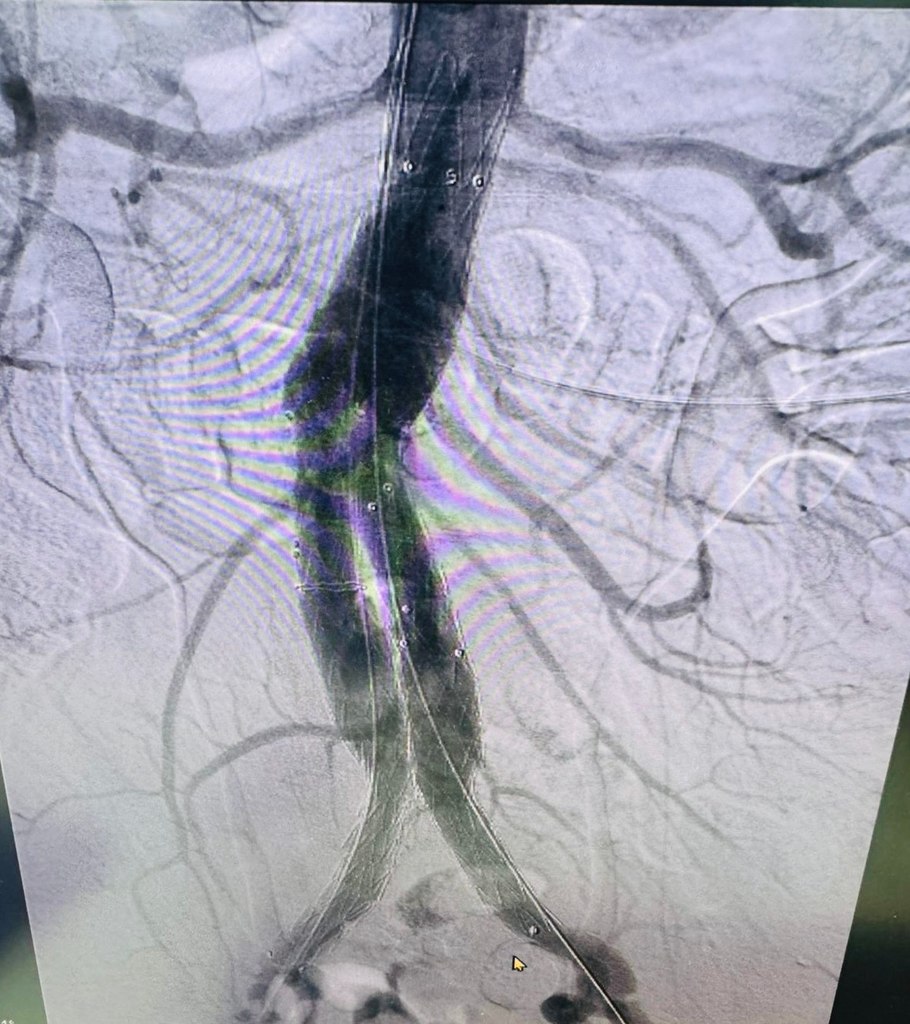

В Региональном сосудистом центре Областной больницы впервые выполнено эндопротезирование брюшной аорты.

Эндопротезирование брюшного отдела аорты — это инновационная малотравматичная методика, которая позволяет:

Операция выполнена руководителем центра Андреем Куликовым, заведующим отделением сосудистой хирургии Игорем Гладковым, заведующим отделением рентгенхирургических методов лечения и диагностики Андреем Колуновым и врачами отделения сосудистой хирургии.